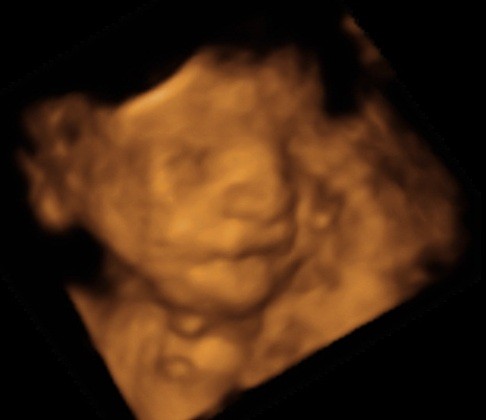

ślicznyNie wiem, ktory temat odpowiedni, wiec wstawie fotki naszego synka tutaj (nie sa to medyczne skany, wiec watek lekarski chyba nie pasuje, nie sa to tez zdjecia brzuszka...)

Zobacz załącznik 435455

Zobacz załącznik 435456

Zobacz załącznik 435457

Zobacz załącznik 435458

Zobacz załącznik 435459

Powiedzcie do ktorego tyg ciazy mozna robic usg 3D?